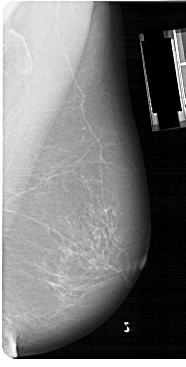

A_1149_1.RIGHT_MLO

RIGHT_CC LINES 5491 PIXELS_PER_LINE 2671 BITS_PER_PIXEL 12 RESOLUTION 43.5 NON_OVERLAY

RIGHT_MLO LINES 5491 PIXELS_PER_LINE 2776 BITS_PER_PIXEL 12 RESOLUTION 43.5 NON_OVERLAY